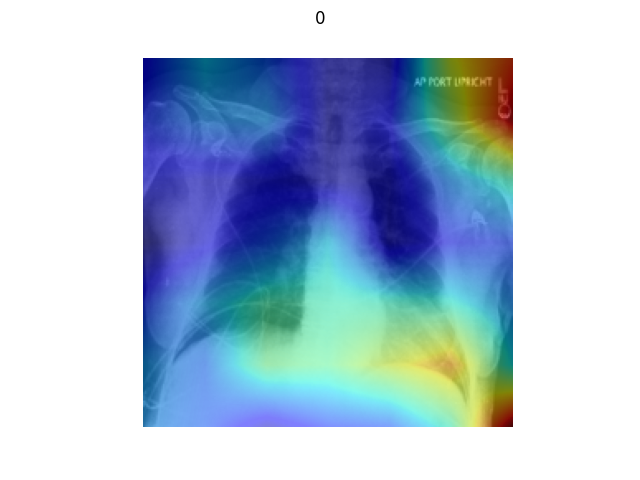

3.2.6. Visual Explanations

As a special test type, visual explanation tools can provide richer information for evaluating the performance of the model than pure error rates. As discussed by (Selvaraju et al., 2017), visual explanations can help users identify error modes, gain trust when establishing and deploying models, and learn more about the model based on its predictions. In Figure 6, we demonstrate several visualizations for Resnet50 on the Chexpert dataset using the Grad-CAM method. The test here is conducted based on the hypothesis that ’perturbation by the basic operators in low contribution regions change the label with low probability AND perturbation by the basic operators in the high contribution regions change the label with high probability.’ With this hypothesis, users can evaluate the correctness of the prediction using their subjective cognition of semantic meaning.

The datasets we use to generate test cases are from the Chexpert paper (Irvin et al., 2019) and the Camelyon17 challenge (Litjens et al., 2018). As shown in Figure 16 and 17, the models are very sensitive to test cases generated by the central occlude operation. This supports the hypothesis that central regions are important regions for the semantic label, especially for some medical imaging datasets. In Figure 18, we conduct visual explanation on the counterfactual analysis. In the counterfactual examples, generated following (Chang et al., 2018), the regions that contribute most to the model’s prediction are blurred with infilling algorithms automatically.